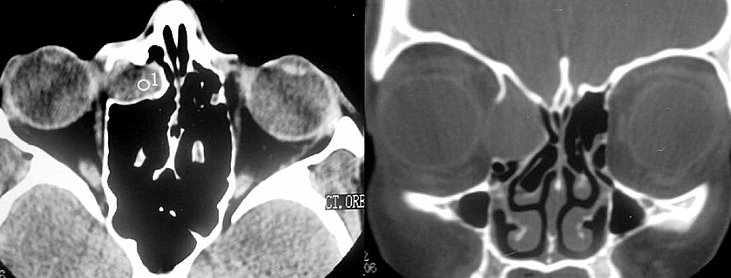

Tudo transcorria se forma tranquila. Mas, no final do ano passado (2021) após uma consulta oftalmológica, foi constatada uma "lesão" no olho direito (crescimento da pele ao lado do olho) após exame de ressonância, com a necessidade de fazer uma cirurgia para retirada desse "corpo estranho.

Ressonância indicando o agravamento do problema.

O procedimento foi realizado no Hospital São Francisco. Mas, pouco tempo depois, agora em abril, em um retorno médico, foi feita uma nova ressonância onde constatou-se que a doença estava de volta e desta vez mais agressiva, atingindo a parede nasal, a órbita e parte do globo ocular direito.